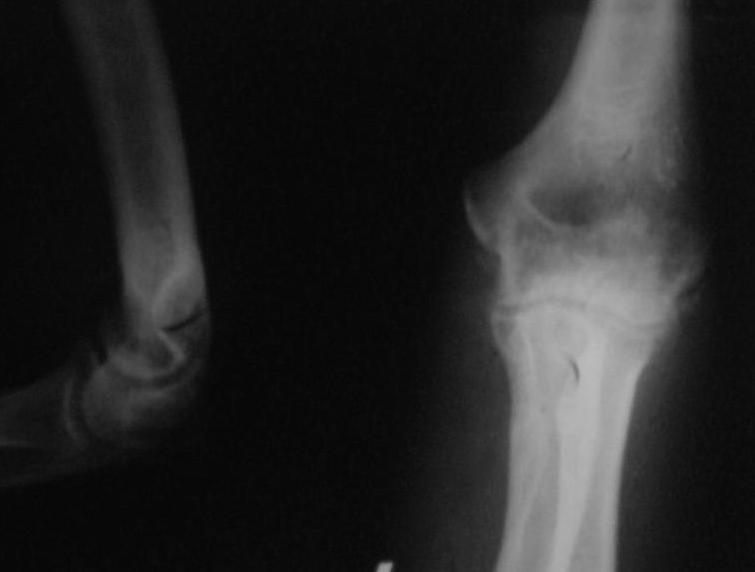

Поступил пациент, 47 лет. травма 15 сентября - вывих предплечья, репозиция. Фиксация 1 месяц. До настоящего времени не обращался. Вот рентенограммы на 2-й и 3-й месяцы после травмы. Неврологии нет. Имеется контрактура локтевого сустава (сгибиние 90, разгибание 120). На снимках что-то похожее на гетеротопические оссификаты, такое впечатление. Как лучше восстановить функцию, возможно ли применить редрессацию? Все-таки локтевой сустав "капризный".С ув. Sergey Melashenko, г. Запорожье

Для суждения о гетеротопических оссификациях нужны снимки хорошего качества, а не то, что есть. Или преобразуйте их в photoshop.